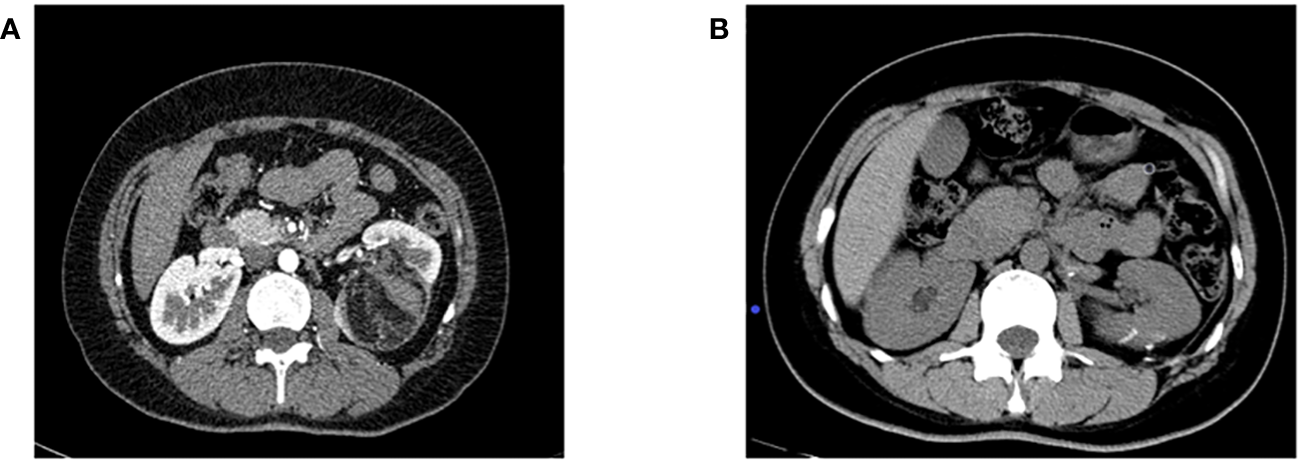

Efficacy evaluation: Serum creatinine was reviewed at 1, 3, and 7 days after surgery, and renal GFR was reviewed at 6 months after surgery. Enhanced abdominal CT was reviewed at 1, 3, 6, and 12 months after surgery and once a year after surgery to confirm tumor recurrence. Postoperative imaging review was shown in Figure 1 (picture of only one typical case was taken). Patients with renal insufficiency were followed up using enhanced MRI. Surgical success was defined as complete resection of the tumor during the operation, no significant tumor lesion was found in imaging examination 3 months after the operation, and no surgical method was changed. Success rate of operation = number of successful cases/number of surgical cases × 100%.

(A) Preoperative enhanced CT imaging results; (B) CT results of the patient 6 months after surgery.